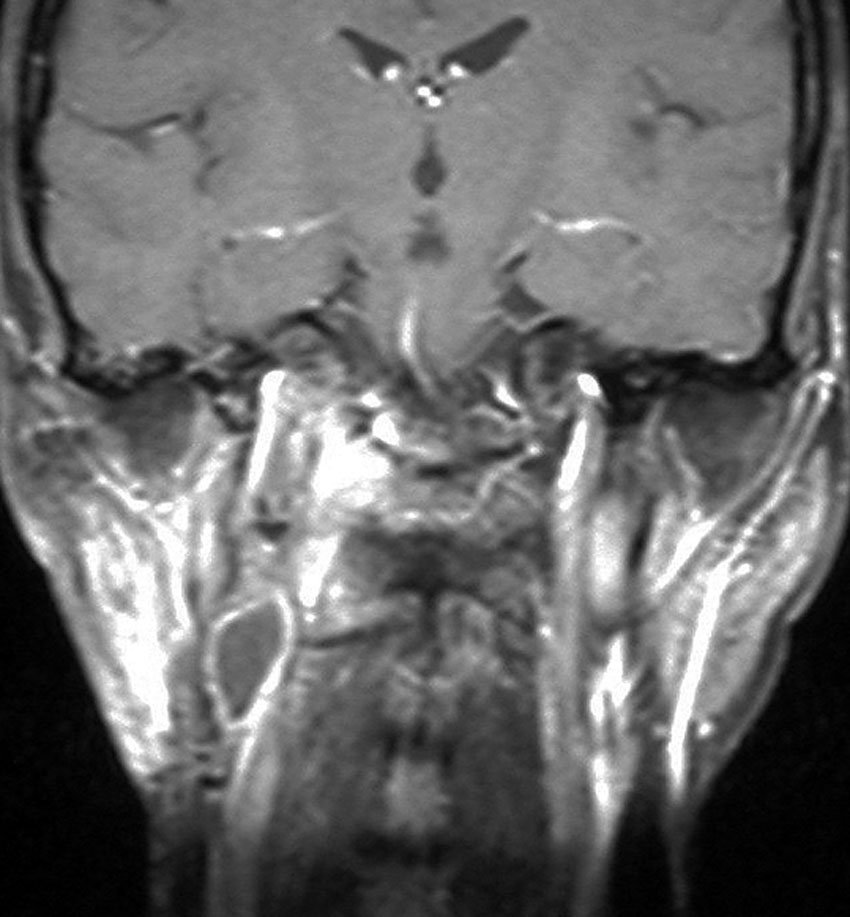

左は1991年,右は2006年のMRI画像です。15年間で腫瘍のサイズは変わっていません。

1991年に50代の女性にみつかったものでした。黄色に示したルートで摘出できないわけではありませんが,右後頭部が腫れてきたという訴えとホルネル症候,軟口蓋麻痺しかなかったので,何も治療しないでほっておきました。2016年まで25年間観察し続けました。症状の悪化は全くなく元気に暮らしておられます。グロームス腫瘍はある一定の年齢になると増大しないという性質を持っている良性腫瘍です。これを大々的な頭蓋底外科手術で摘出するするという愚を犯してはなりません。